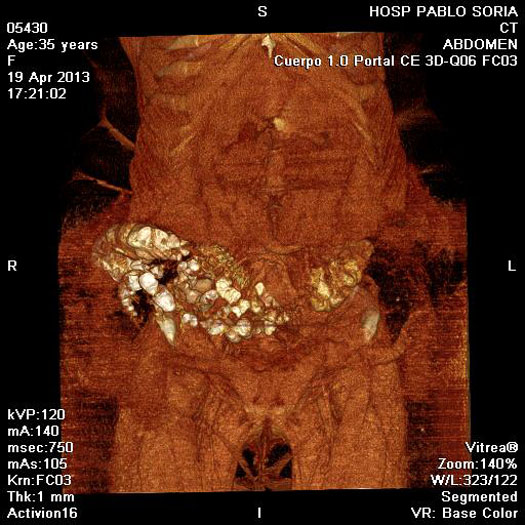

TAC

Paciente femenina, 45 años de edad, IMC > 35, (>) ingresa tras sufrir un accidente automovilístico por volcamiento. Sentada en el asiento de atrás con cinturón de seguridad a dos dedos en la cintura. Luego de 14hs del accidente ingresa al servicio de emergencia, lúcida, Glasgow 15, con dolor intenso en miembro inferior izquierdo y tatuaje de cinturón de seguridad a nivel de pelvis. Se realiza TAC de emergencia y se somete a una laparoscopia diagnóstica por descenso del Hto en 5 puntos. Se reconvierte a una laparotomía media , se sutura el mesosigma desgarrado y una laceración del sigma. Se constata hernia traumática con sección completa de pared anterolateral del abdomen. Se deja Abdomen abierto y contenido.